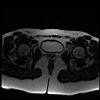

bekken